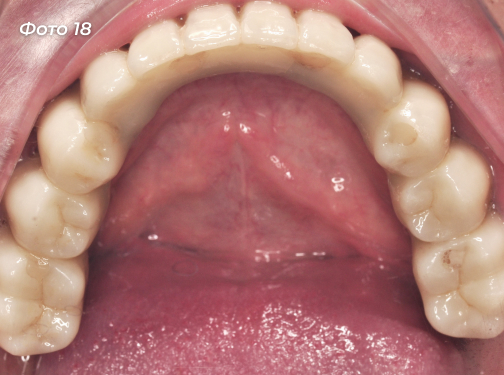

Установлены постоянные конструкции на верхней и нижней челюстях (Фото 18, 19, 20, 21).